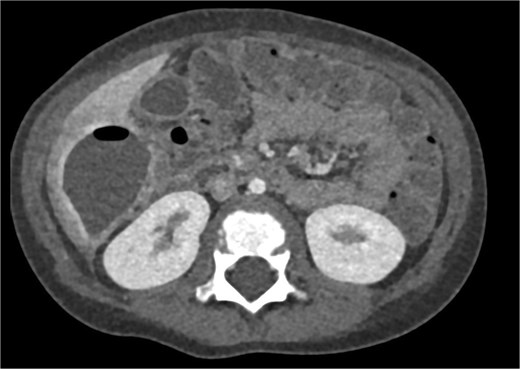

CT imaging of the abdomen (Fig. 2) revealed a retrocecal appendix in its typical location, measuring 50 mm in length and 14 mm in diameter, with a thickened wall (5.5 mm). A proximal fecalith measuring 3 × 3 × 14 mm was identified. Post-contrast enhancement of the appendix wall was noted. Adjacent to segments V and VI of the liver, a fluid collection with an air-fluid level was observed, measuring 5.3 × 3.8 × 4.5 cm, surrounded by a 3 mm enhancing capsule, consistent with a hepatic abscess. A second, smaller hypodense collection measuring 13 × 22 × 11 mm was found inferior to the primary abscess. Additional findings included reactive lymphadenopathy (up to 8 × 4 mm) and free fluid in the right iliac fossa (up to 12 mm). Other abdominal organs, including the liver, pancreas, kidneys, and spleen, appeared normal. The findings were consistent with complicated acute appendicitis and associated abscesses.

CT imaging of acute appendicitis with fecalith and multiple hepatic abscesses.